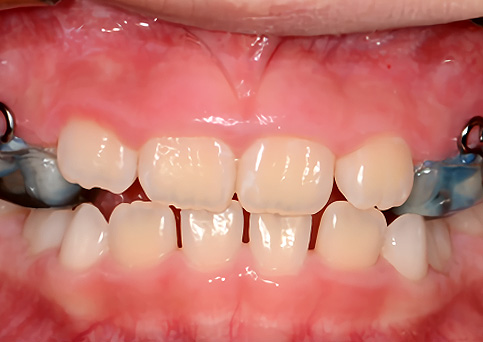

Anterior Cross bite

반대교합(주걱턱 예방)

주걱턱

주걱턱, 조기에 예방할 수 있습니다.

페이스마스크를 활용한 악정형 장치로 앞니 반대교합을 개선하고, 주걱턱을 미리 예방할 수 있습니다. 적절한 시기의 예방교정을 통해 자연스럽고 건강한 치열로 성장할 수 있도록 도와주었습니다.

• 주증상

전치부 반대교합

• 치료기간

약 6개월

• 부작용

치아표면의 탈회, 치은 부종, 치근흡수 등의 부작용이 있을 수 있습니다.